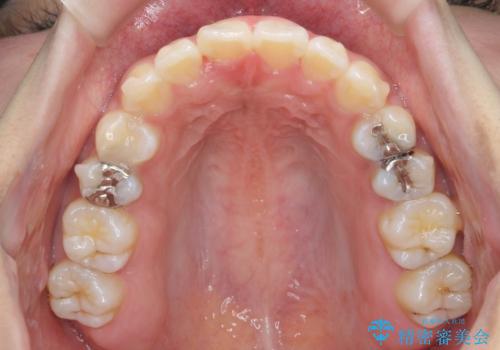

- 矯正装置

- インビザライン

- 治療期間

- 1年4ヶ月

- 治療回数

- 10-30回